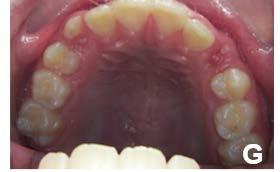

58 | CASO CLÍNICO

Tratamiento de mordida profunda, con arco utilitario, en paciente en crecimiento